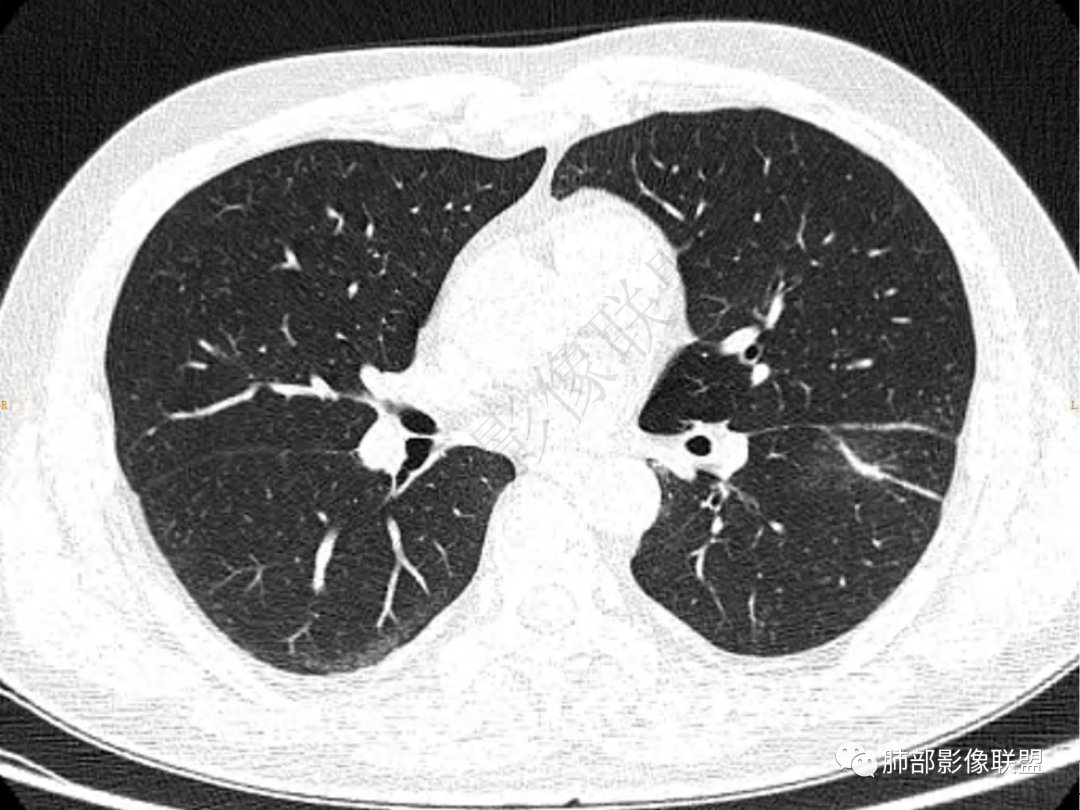

2.左肺下叶团片影,跨背段及内前基底段,实性部分类椭圆形,密度不甚均匀,可见毛刺及棘状突起,未见典型分叶及胸膜凹陷。病灶上下缘可见相应肺段支气管旁进侧出,管壁轻度增厚,未见狭窄阻塞。

3.周边较大范围磨玻璃影,边界相当模糊,小叶增厚明显。注意叶裂另一侧、左肺舌段亦可见磨玻璃影及增厚的小叶间隔。未见明确卫星病灶。

1.病灶不够密实,没有典型分叶,收缩乏力等,支气管未见截断等,缺乏一般肿瘤性肿块特征。

2.周围磨玻璃影边界不清缺乏限制,甚至“激惹”到相邻肺叶,也许提示较明显的炎性水肿。